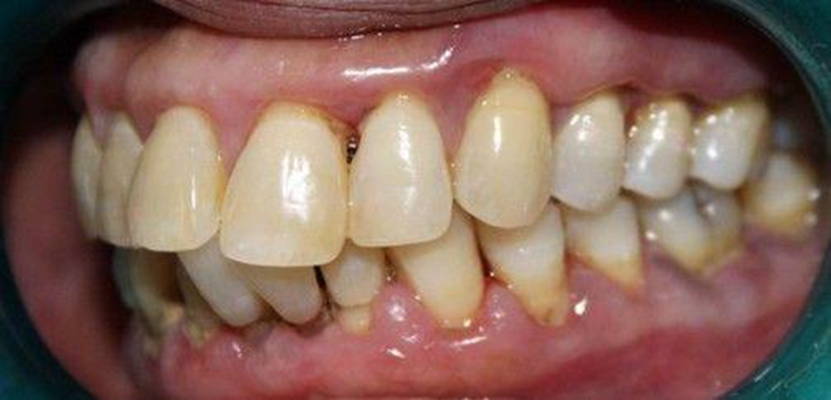

牙周炎圖片

牙周袋 (7)